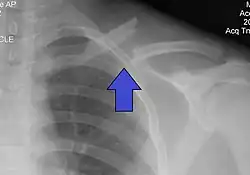

The basic method to check for a clavicle fracture is by an X-ray of the clavicle to determine the fracture type and extent of injury. In former times, X-rays were taken of both clavicle bones for comparison purposes. Due to the curved shape in a tilted plane X-rays are typically oriented with ~15° upwards facing tilt from the front. In more severe cases, a computerized tomography (CT) or magnetic resonance imaging (MRI) scan is taken. However, the standard method of diagnosis through ultrasound imaging performed in the emergency room may be equally accurate in children.[6]